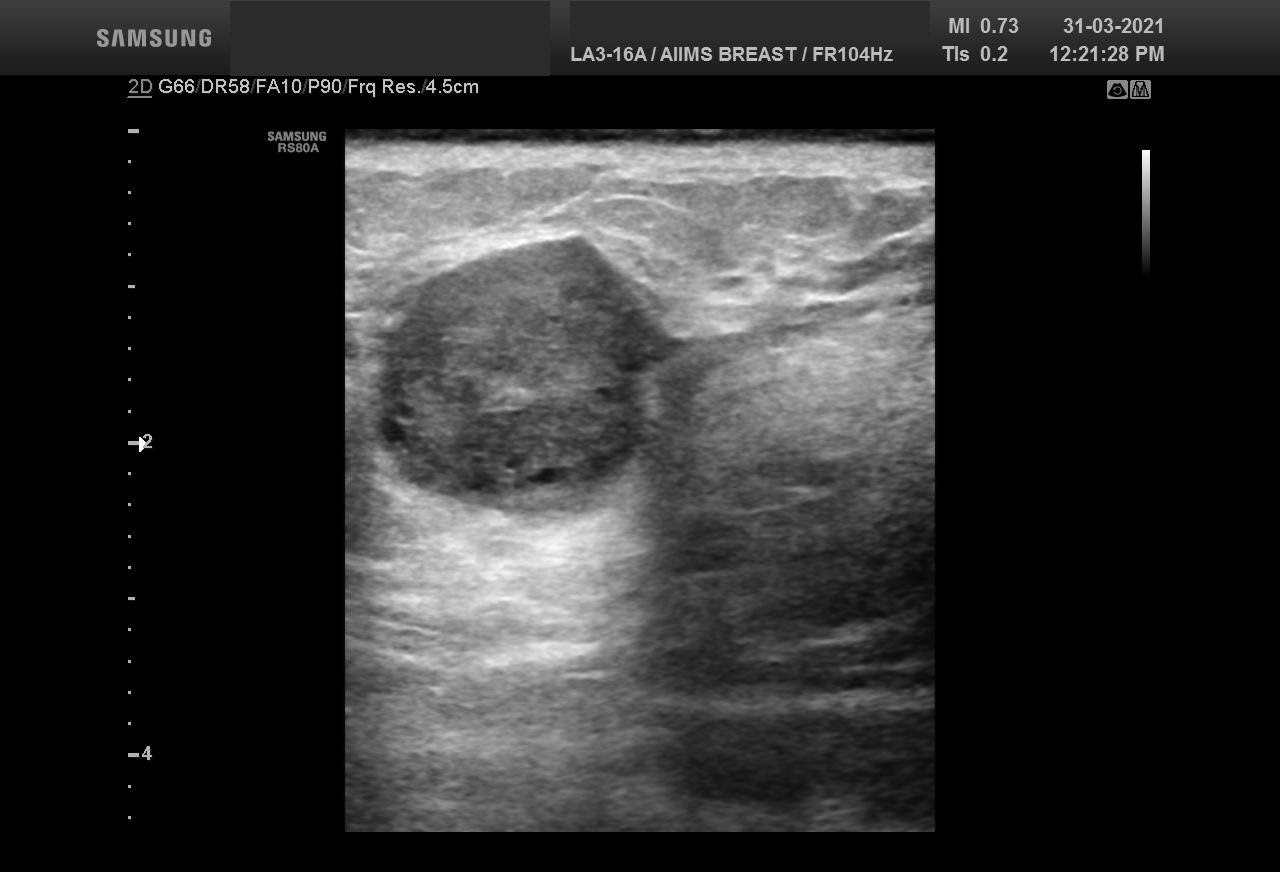

Bilateral Digital mammography , Craniocaudal (CC) and Mediolateral oblique (MLO) view with tomosynthesis images revealed a round shaped, equal density mass with indistinct margin in lower outer quadrant. No suspicious microcalcifications was seen. No significant axillary lymph nodes were present. A high resolution ultrasound of the right breast showed a round shaped, heterogeneously hypoechoic mass with irregular margin, small cystic spaces within and posterior acoustic enhancement, measuring about 1.6x1.9x1.5cm at 7 O’clock position. Mild internal vascularity was noted on colour doppler images. Right axilla showed suspicious lymph nodes with loss of fatty hilum and thickened cortex.

Although the mass has few benign features like round shape and posterior enhancement, presence of irregular margin and axillary nodes with thickened cortex and loss of fatty hilum points towards the suspicious nature of the mass. So, the mass was classified as BIRADS category 4b lesion. Ultrasound guided biopsy of the mass was suggestive of invasive breast carcinoma with possibility of medullary carcinoma. IHC study showed tumor to be Positive for PR and negative for ER and HER2neu receptors. Patient underwent Breast conserving surgery with right axillary lymph node dissection and final histopathological report was Invasive carcinoma with medullary features. Axillary lymph nodes were involved by the tumor.